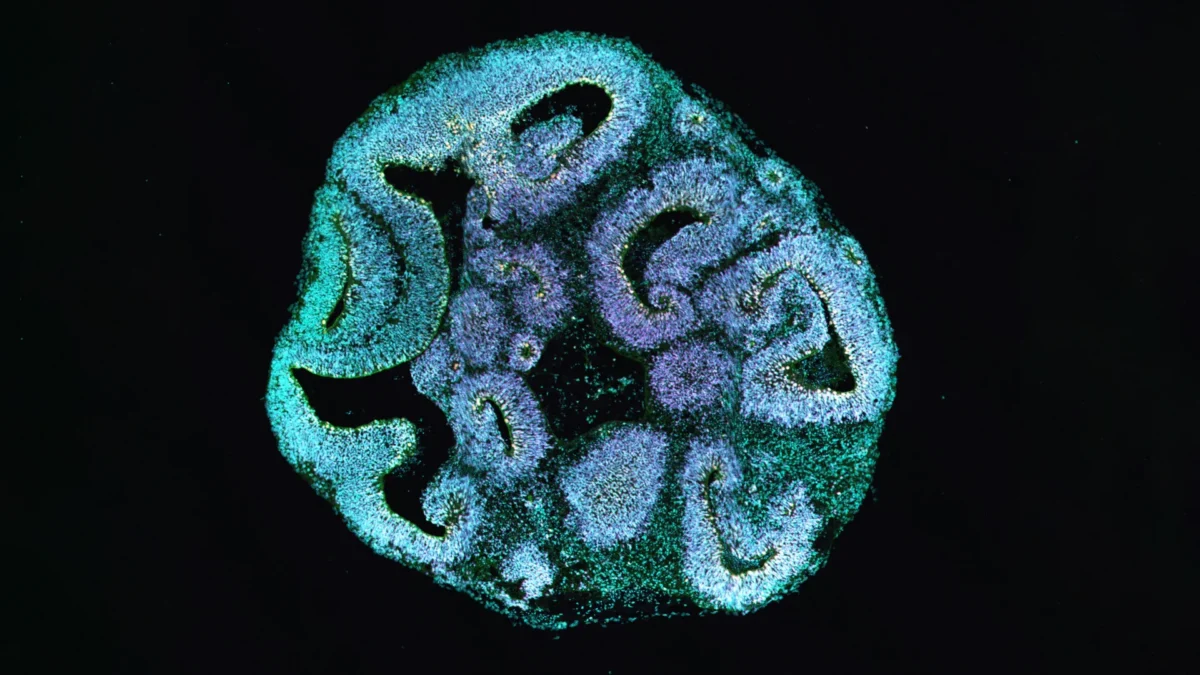

A actina desempenha um papel central no citoesqueleto, a estrutura interna que confere forma às células e ajuda na movimentação de materiais dentro delas. Em pessoas com síndrome de Baraitser-Winter, uma mutação afeta um dos dois genes de actina cruciais. Para entender as consequências, os pesquisadores reprogramaram células da pele de pacientes afetados em células-tronco pluripotentes induzidas. Essas células-tronco foram então utilizadas para cultivar organoides cerebrais tridimensionais que imitam os estágios iniciais da formação do cérebro humano.

Após trinta dias de desenvolvimento, as diferenças eram notáveis. Os organoides cultivados a partir das células dos pacientes eram cerca de 25% menores do que aqueles cultivados a partir de células de doadores saudáveis. As regiões semelhantes a ventrículos dentro dos organoides, onde as células progenitoras se reúnem e começam a formar as primeiras células nervosas, também eram significativamente menores.